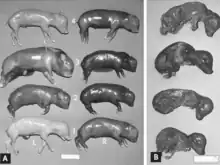

Macroscopic changes of embryos are death followed by resorption of fluids (Fig. 4) and then soft tissues (Fig. 5). Virus and viral antigen are widely distributed in tissues of infected embryos and their placentas,[84] and it is probable that microscopic lesions of necrosis and vascular damage, subsequently described for fetuses, also develop in advanced embryos.

There are numerous macroscopic changes in fetuses infected before they become immunocompetent (Fig. 6). These include a variable degree of stunting and sometimes an obvious loss of condition before other external changes are apparent; occasionally, an increased prominence of blood vessels over the surface of the fetus due to congestion and leakage of blood into contiguous tissues; congestion, edema, and hemorrhage with accumulation of serosanguineous fluids in body cavities; hemorrhagic discoloration becoming progressively darker after death; and dehydration (mummification). Many of these changes also apply to the placenta. Microscopic lesions consist primarily of extensive cellular necrosis in a wide variety of tissues and organs[95][98] (Fig. 7A). Inflammation[98] and intranuclear inclusions[95] also have been described.